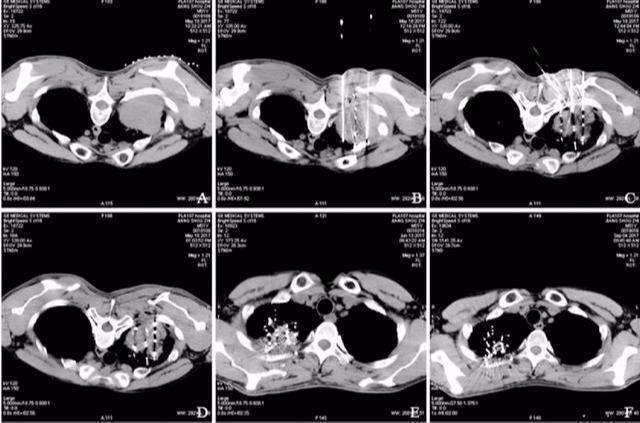

71岁的王大爷是退伍军人,因为咳嗽伴咳血在医院检查出右肺癌,住院后王大爷以最快的速度完善了术前相关检查,进行了右肺癌根治术,手术恢复得很顺利。不幸的是3年后肿瘤再次复发,与3年前相比王大爷的身体已经大不如前,加之做过一次手术胸膜腔黏连严重,如果再次手术难度太大。王大爷的家人也走访了全国最好的医院最后决定进行全身化疗加局部放疗的治疗方案。

王大爷的家人听到将具有放射性的物质放入人体内后极力反对,甚至对医生产生了极大的不信任。在我们一次又一次的解释下,加之他们自己搜索了相关文献,最终决定试一试。不试不知道,一试吓一跳。每次复查王大爷的肿瘤都在缩小,终于在粒子植入6月后,肿瘤奇迹般地消失了。

在CT引导下,采用经皮穿刺方式将放射性粒子植入肿瘤内(用一根穿刺针将粒子植入肿瘤内),或手术将碘125粒子植入肿瘤内或可能受肿瘤侵犯的组织内,也可以植入到肿瘤转移的淋巴结内。其中最常用的还是经皮肺穿刺技术,损伤小痛苦小,是目前最主要的方法。